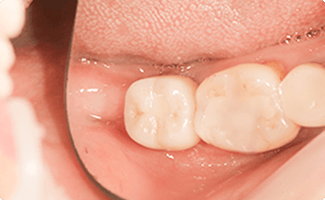

一番奥の入れ歯が噛みにくい方

BEFORE

AFTER

症例概要

年代・性別

50歳代 女性

主訴

奥歯で噛めない

治療内容

右下6番インプラント治療

治療期間

3ヶ月

治療のリスク

骨の状態によっては骨造成が追加で必要な場合があります。

メンテナンスやセルフケアの状態でインプラントの歯周病に犯される場合があります

治療費用

407,000円(税込)